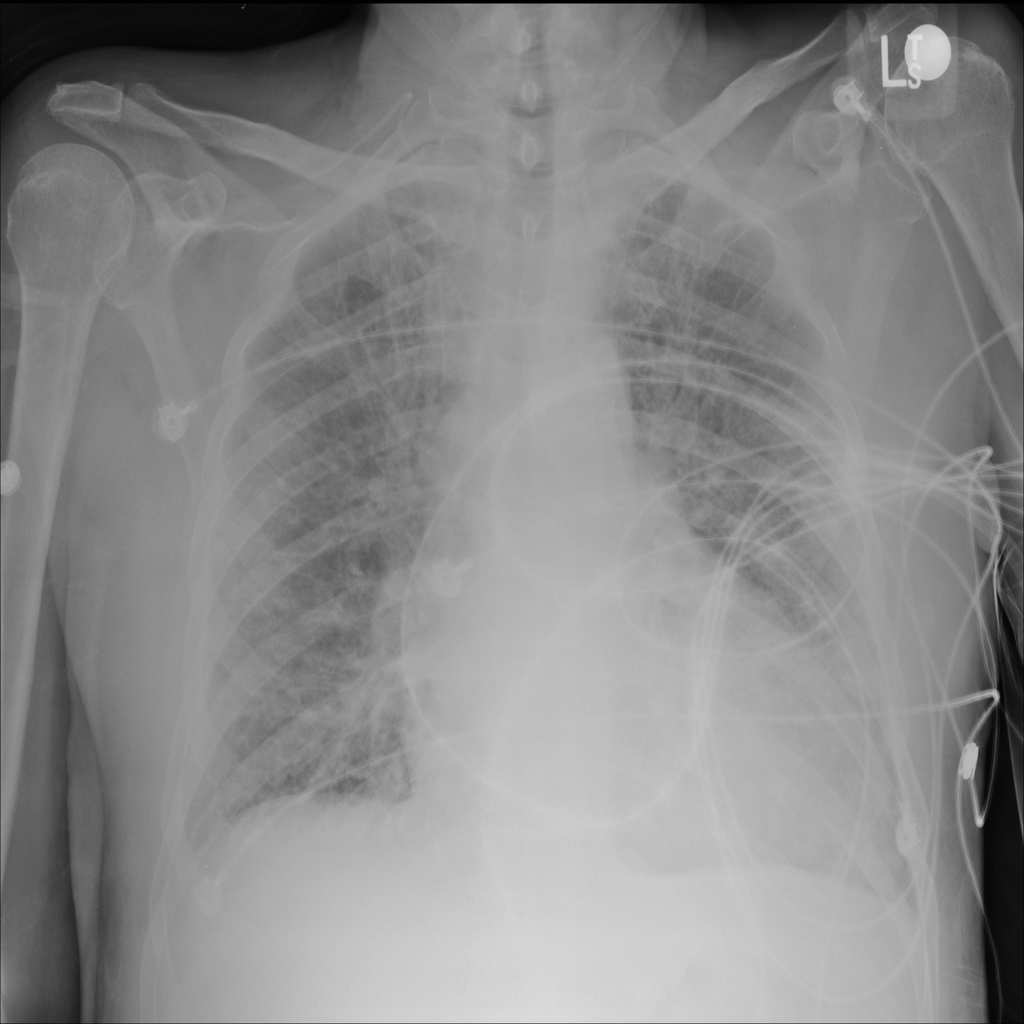

PAT-E828 · IMG-004Edema

PAT-E828 · IMG-004

AP